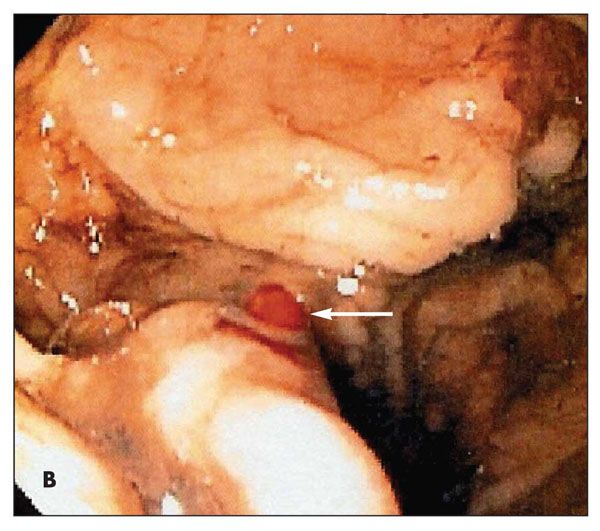

A 70-year-old man presented with dyspnea, weakness, and lightheadedness 2 days after he was treated for suspected GI bleeding. An esophageal ultrasonogram showed a bleeding artery at the proximal fundus. Esophagogastroduodenoscopy revealed a small, red, nipple-like lesion in the proximal stomach (arrow). A histological section showed a tortuous, thick-walled blood vessel that extended through the gastric submucosa into the overlying luminal epithelium.

The ruptured vessel demonstrated necrosis, erythrocyte extravasation, and clotting with adjacent acute inflammatory exudates. The findings were consistent with Dieulafoy lesion, which is responsible for 0.3% to 6.7% of upper GI bleeding.

Patients often present with a massive upper GI hemorrhage and recurrent painless bleeding associated with severe life-threatening hemodynamic involvement. Dieulafoy lesions may be found in any portion of the GI tract. The diagnosis is based on endoscopy.